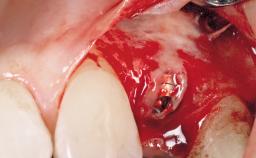

Late Placement of an Implant in a Maxillary Left Central Incisor Site

A 36-year-old female patient was referred for the replacement of the upper left central incisor (tooth 21), which had fractured. Although the tooth had been asymptomatic for many years, the crown began to loosen, at which time she presented to her dentist for an assessment. Teeth 21 and 22 had both been endodontically treated many years previously. She was a healthy individual and a non-smoker.

Bone Augmentation Horizontal|Staged

Augmentation Materials Xenogenous|Membrane

Soft Tissue Grafting Simultaneous